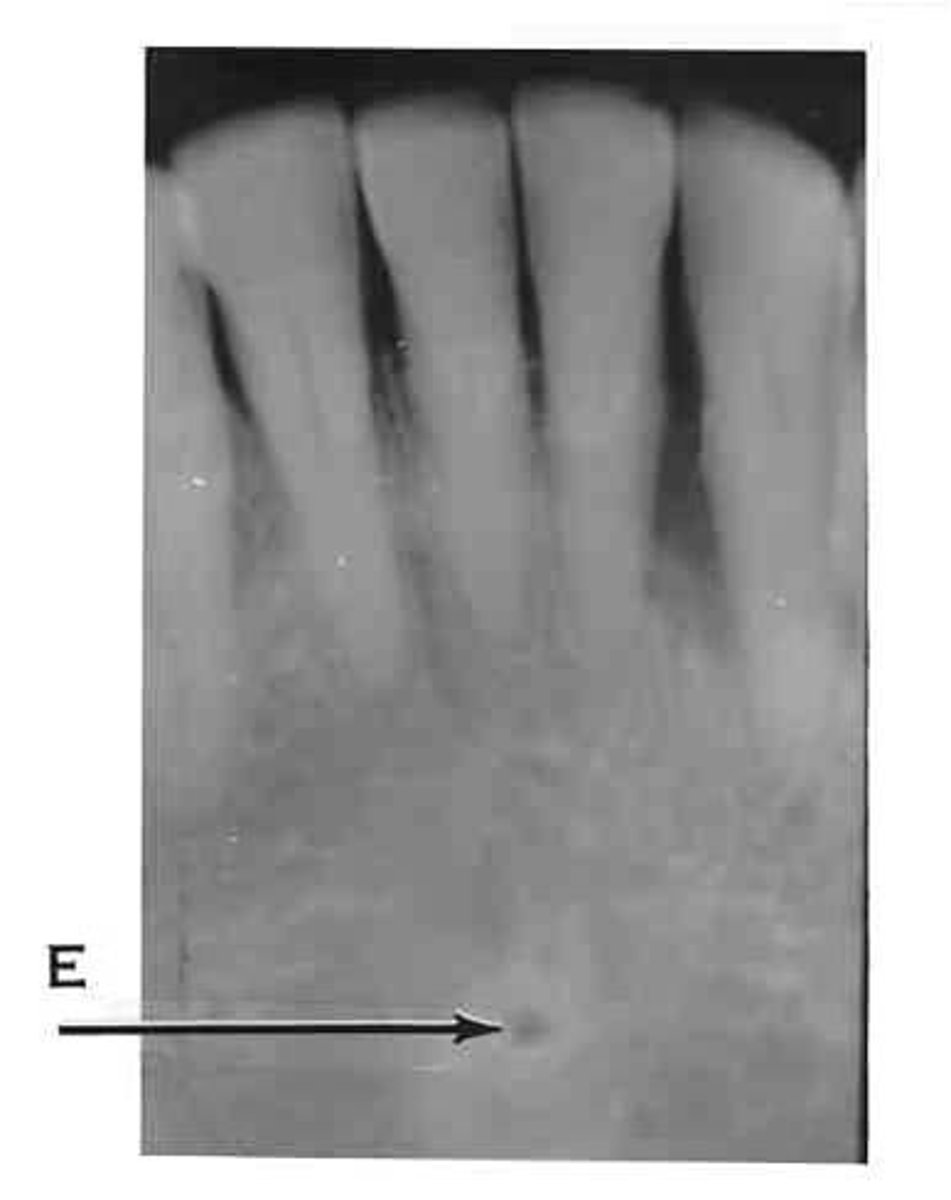

Mental foramen

What is the radiolucent structure seen here?